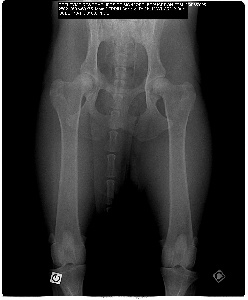

voici la radio de la hanche de D'Nara